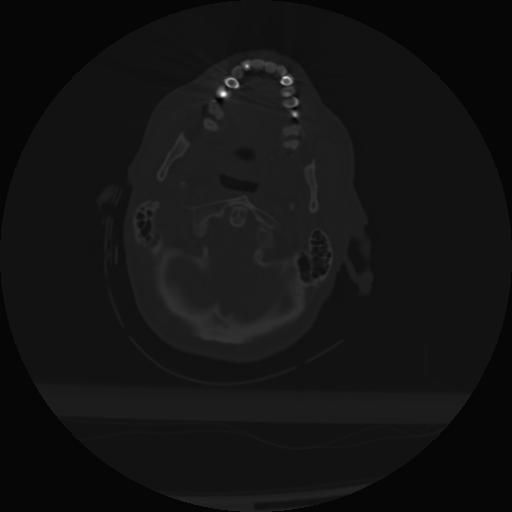

21 ANGIO,CE,Axial,3.0,ANGIO,,